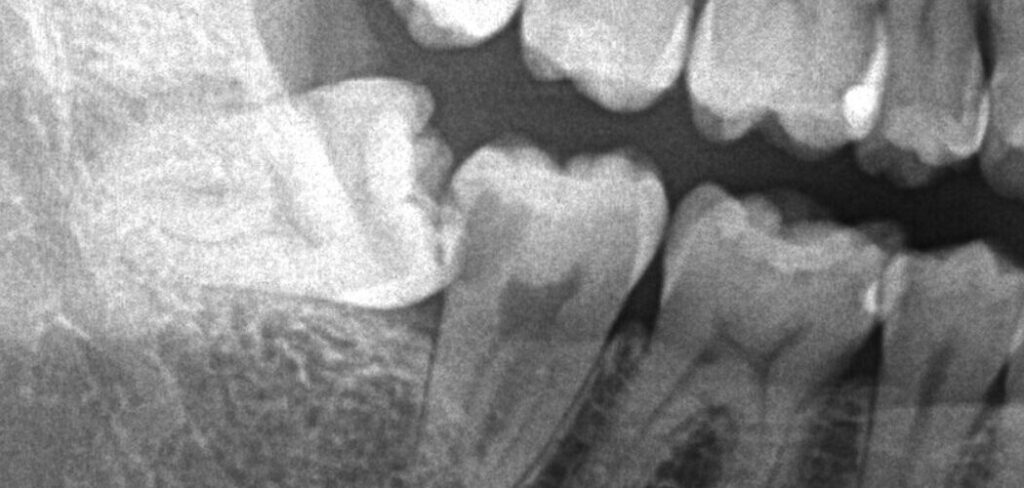

患者様は親知らずが痛み来院されました。レントゲン検査で調べた所、一つ前の歯(大臼歯)に大きな虫歯が認められたため、治療の必要性とメリットデメリットをお話しし、ご本人様は再発率の低い治療をご希望されました。

精密に治療するためにはまずはVPT(歯髄温存療法)を行い神経を温存し、根管治療を回避、その後親知らずを抜歯して間を空けずにオーバーレイ(テーブルトップベニヤ)を作成していく必要があります。患者様と綿密にスケジュールを練り、施術に挑みました。